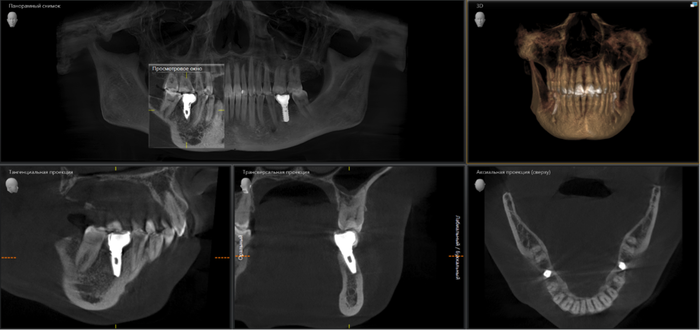

Ниже, на панорамном снимке зубов, мы наблюдаем критичную убыль костной ткани вокруг имплантатов на верхней челюсти.

Оранжевая пунктирная линия - было,

красная - стало.